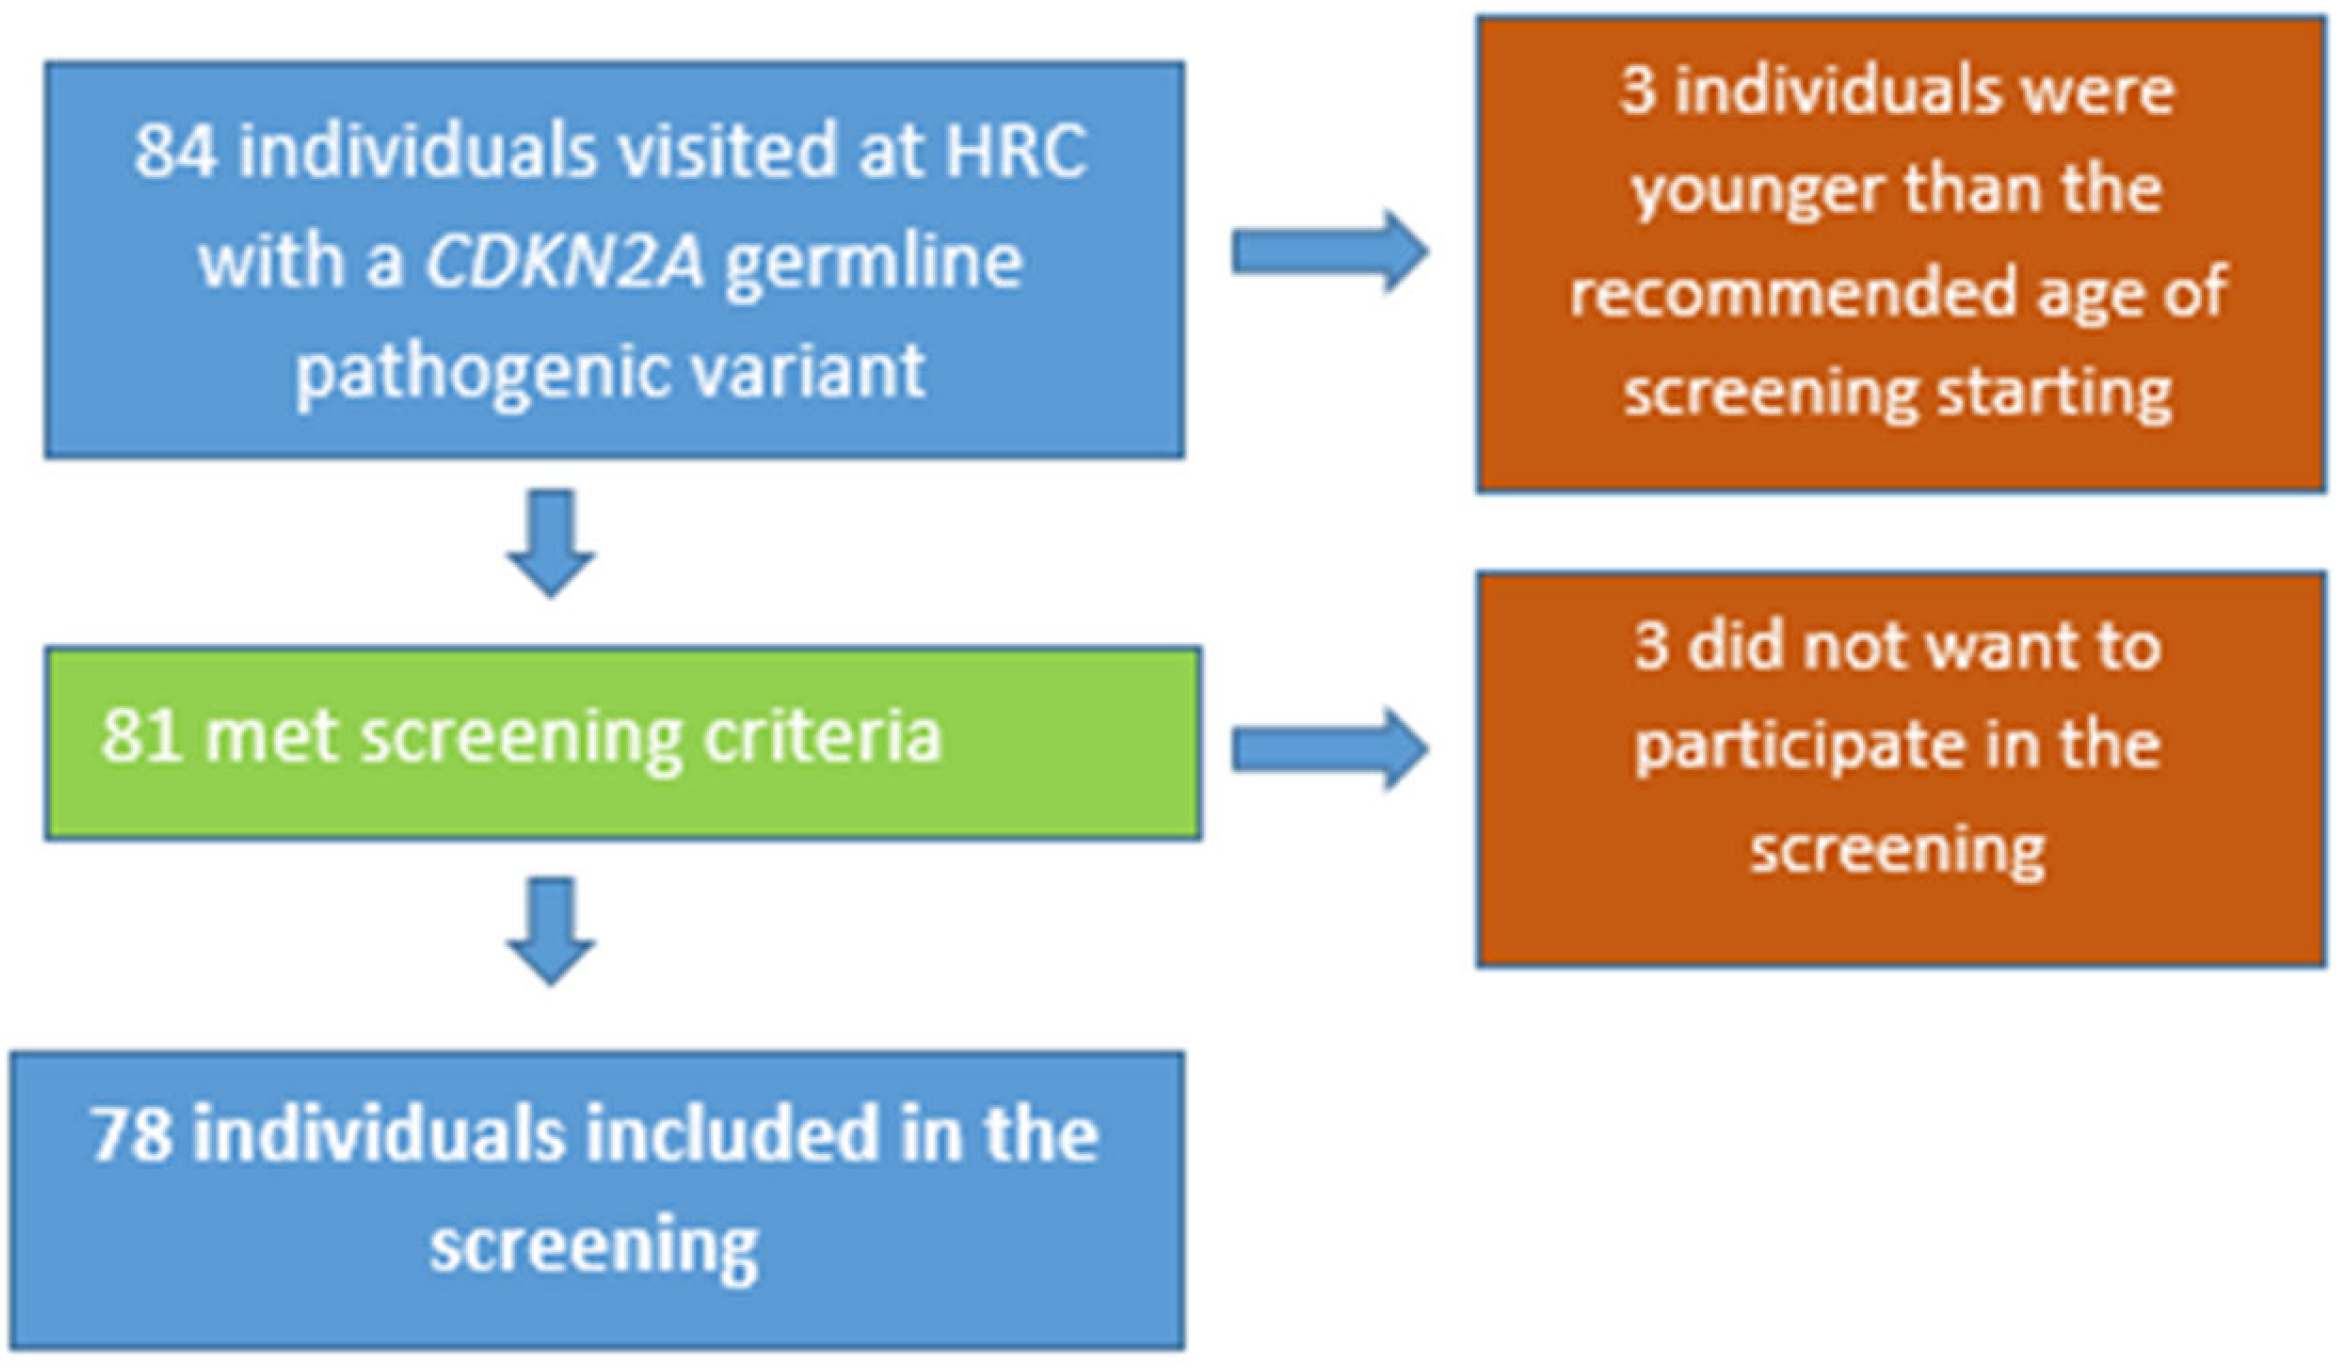

2.1. Study Population

3. Results

3.1. General Characteristics

3.2. Pancreatic Cancer Surveillance Program: Characteristics and Findings